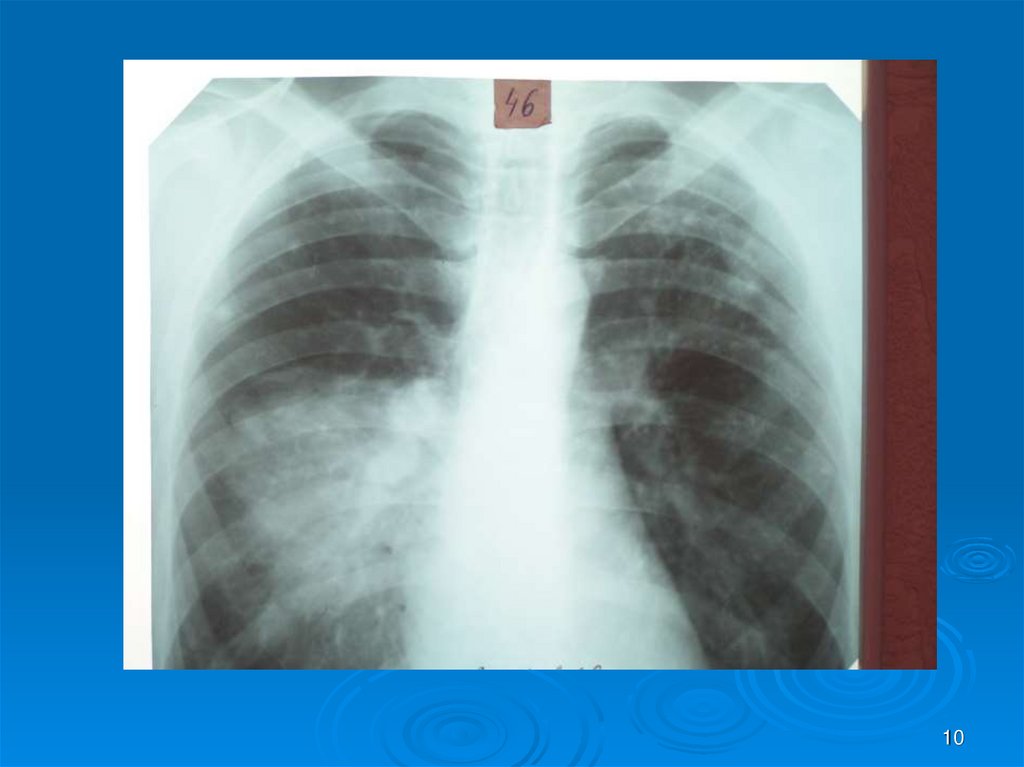

10.

10